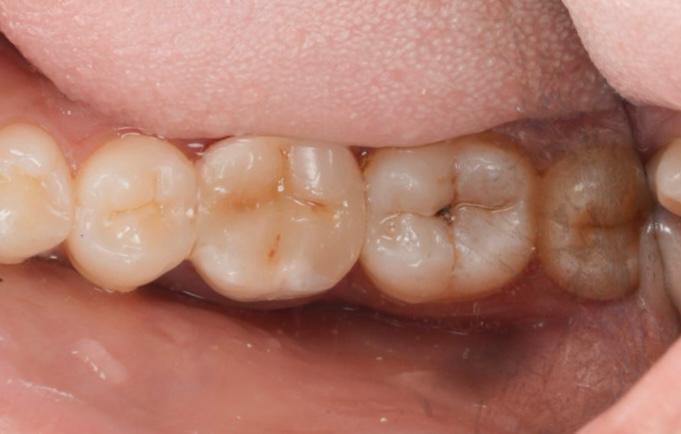

Clinical and Radiographic Findings

- Inadequate root canal obturation with voids.

- Missed canal anatomy suspected.

- Overhanging proximal restoration and subgingival distal margin.

- Associated periapical radiolucency.

- Compromised coronal seal.

- Thick secondary dentin and occlusal attrition pattern.